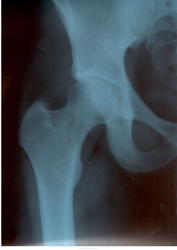

1. Деформирующие коксартрозы Iст. по Косинской здесь можно ставить с двух сторон.  IIст. по каким-то зарубежным неразумным классификациям может быть. Видимые части крестцово-подвздошных суставов без особенностей.

2. Клинические проявления скорей всего связаны именно с АРС-синдромом. А при деформирующих коксартрозах боли в паху нехарактерны.. И для лечения стоит обратиться к врачу работающему со спортивной травмой.

Коксартроз 2 ст. с 2-х сторон.Налицо неравномерное сужение суставных щелей, субхондральный  склероз по верхне-наружным краям вертлужных впалин.

Однозначно - 1 ст с обеих сторон, справа щель уже чем слева, не нужно гипердиагностики - людям жить еще...))) молодой человек и так уж весь разволновался))) и оперироваться бросаться не стоит, это "палка о двух концах", снять обострение, режим и "грани разумного" в физкультуре и др.

я б вообще норму поставила, не так уж и выражено там склерозирование крыш, и некоторая асимметричность ширины р-суставный щелей вполне допустима.

Снимки «не ах», но неравномерное снижение рентгеновской суставной щели отчётливо. Да и кисточки, если приглядеться, видны.